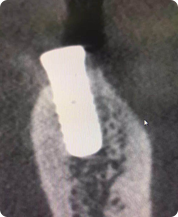

先来看一组CT

这是三个种植牙后在CT里面显现的影像种植牙效果选择